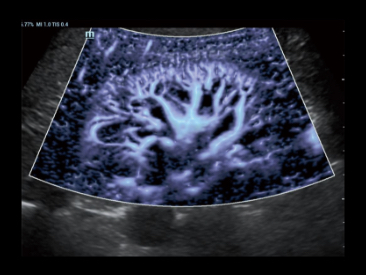

Una nueva forma de demostrar el Color/flujo Doppler de potencia 2D de forma innovadora en una visualizaciĂłn 3D

Caso con Glazing Flow (modo de potencia):

?rbol de la arteria renal.

Glazing Flow ofrece una visualizaciĂłn nĂtida de las arterias arciformes y la estructura de la arteria interlobular menor con visualizaciĂłn en 3D.